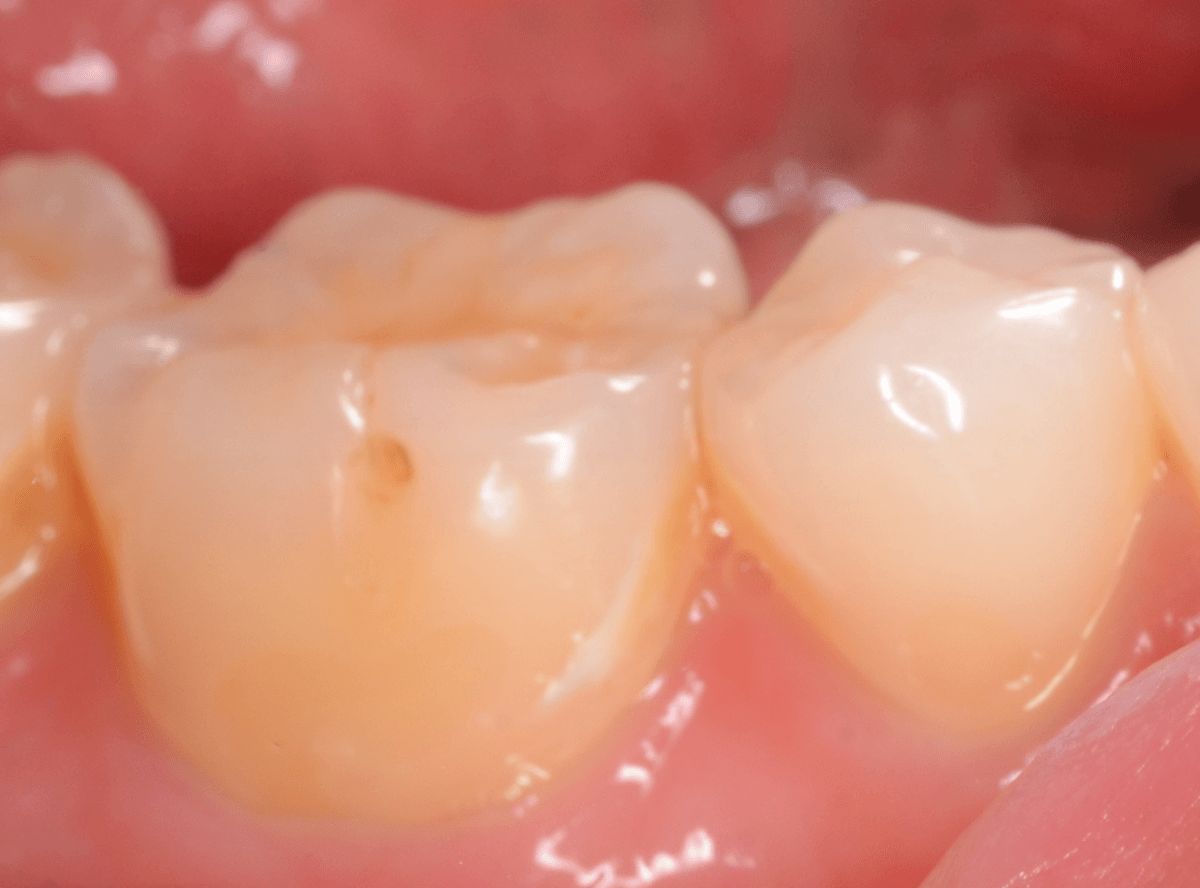

こちらの写真でもわかりづらいですが、摩耗した部分に、レジンを少し盛ってあげる。

これだけで、劇的に症状が治まる事がほとんどです。

今回も、症状は劇的に緩和されました。

ただし、過度な歯ブラシや歯ぎしりが続く場合、レジンも短期間で外れてしまう事も多いですので、歯ブラシの仕方を変えたり、歯ぎしり防止のマウスピースを作るなどの対処も一緒に考える必要があります。